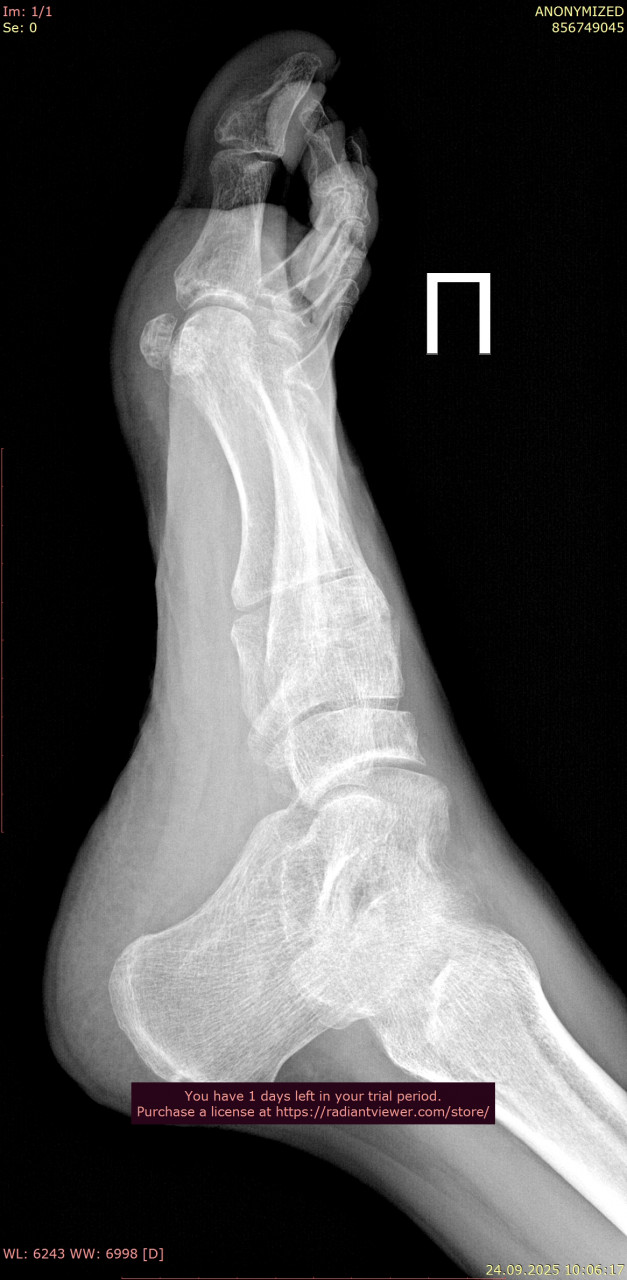

Прикрепляю снимки стопы от даты перелома 23.06.2025 (одна проекция из за лимита файлов на сайте} , и спустя 3 месяца от 24.09.2025. Как Вы считаете, переломы зажили окончательно, проблем быть не должно? В дополнение про выбор стелек: в ортопедическом салоне можно просто сказать, что у меня остеоартроз голеностопного сустава и попросить недорогие стельки по размеру?

Здравствуйте. На новых снимках переломы срослись, кость выглядит восстановленной, грубых осложнений не видно. Проблем при обычной нагрузке быть не должно. В салоне действительно можно сказать про остеоартроз голеностопа и подобрать недорогие готовые стельки по размеру и этого на начальном этапе будет достаточно.